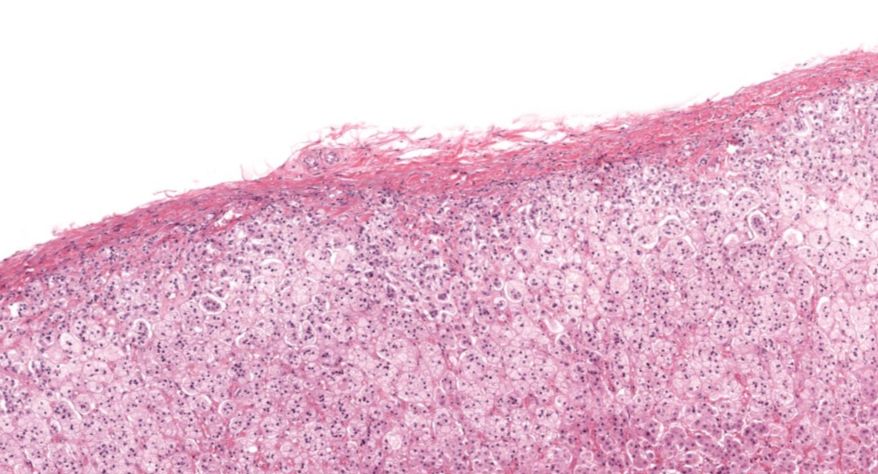

低倍镜观察:1. 被膜:由薄层结缔组织组成。2. 实质:由许多大小不等的滤泡构成。滤泡壁是单层立方上皮细胞,滤泡腔内充满粉红色匀质胶状物,滤泡之间的结缔组织内有丰富的血管。高倍镜观察:1. 滤泡:滤泡壁的单层滤泡上皮细胞一般呈低柱状或立方状,胞质着浅色,细胞核呈圆形。滤泡腔内充满了粉红色匀质胶质。2. 滤泡旁细胞:体积较大,呈圆形或椭圆形;细胞核较大,呈圆形,着色较浅,细胞质染色也较浅。细胞或嵌在滤泡壁上或成团分布于滤泡之间。3. 间质:由结缔组织组成。位于滤泡之间。其中含有丰富的毛细血管及三五成群的滤泡旁细胞。

2.滤泡